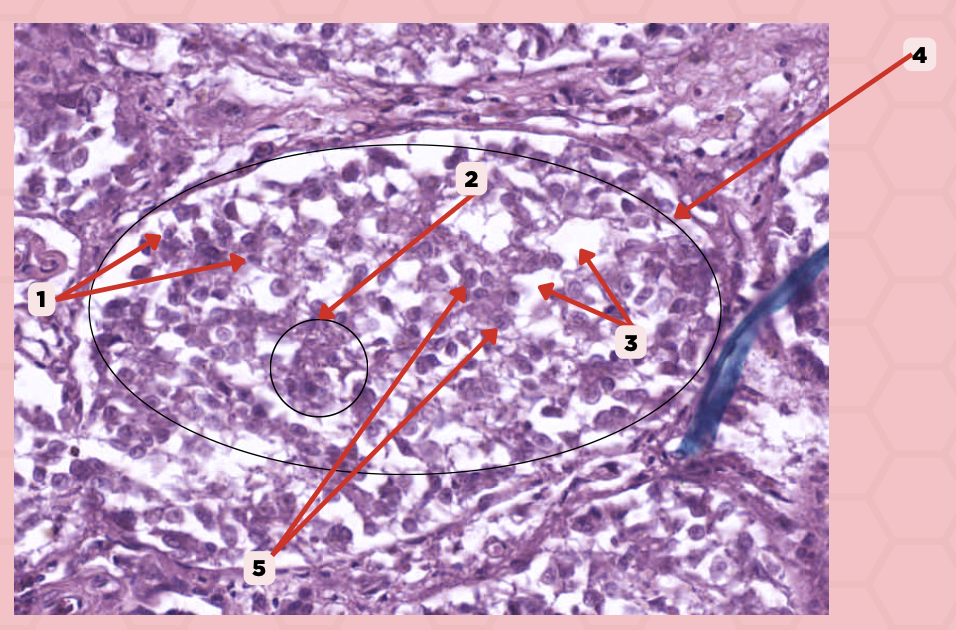

Pancreas

Identify the specimen.

Islets of Langerhans

Identify the structure labeled as 1.

Pancreatic Acini

Identify the structure labeled as 2.

Reticular Tissue

Identify the structure labeled as 3.

Beta-cells

Which cells occupy the central area of #1?

Pancreatic Acini

#3 delineates the pale- staining cells from the darker-staining cells. What do you call the darker-staining cells?